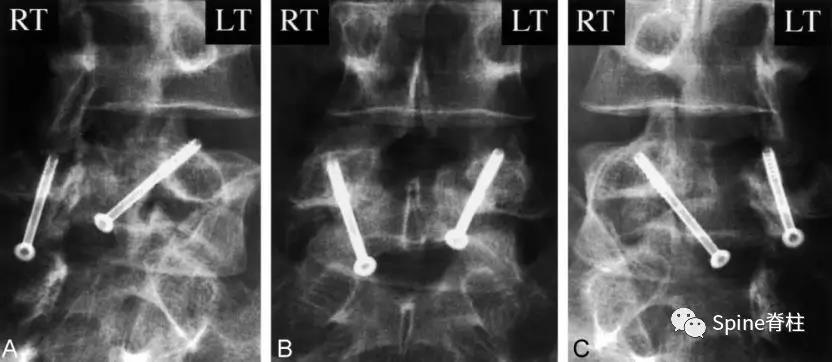

2003年发表在Am J Sports Med杂志(IF=6.20)上的病例报道,很好的阐述了峡部裂和椎弓根裂的变化。描述一个17岁的棒球运动员,运动后腰痛1月余,随访的辅助检查提示相同椎体水平出现的3个连续性应力性骨折:第一次为左侧峡部,第二次为右侧椎弓根,第三次为右侧峡部。

图:起始CT提示L5左侧峡部裂(双箭头),起始CT检查后2个月复查可见出现右侧椎弓根裂(单箭头),4个月复查可见椎弓根裂愈合(单箭头)